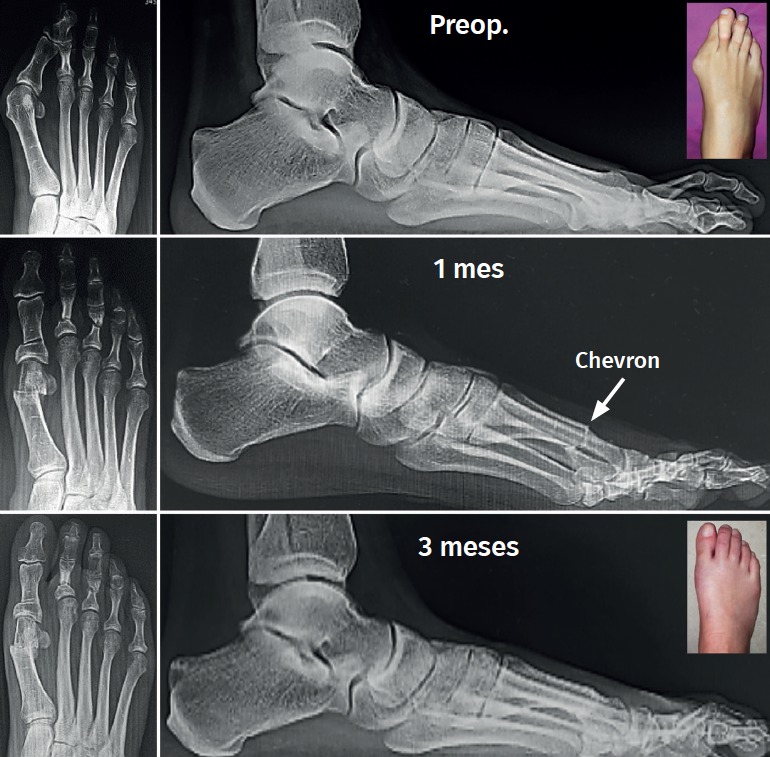

El HV° preoperatorio promedio (DE) fue de 32,67° (6,33). En el postoperatorio al año, el promedio (DE) del HV° fue de 11,51° (5,0), logrando una mejoría promedio del ángulo metatarsofalángico de 21,16° respecto al prequirúrgico.

El IM° preoperatorio promedio (DE) fue de 14,68° (3,26). En el postoperatorio al año, el promedio (DE) del IM° fue de 9,52° (2,58), logrando una disminución promedio de 5,16° respecto al prequirúrgico.

Con respecto a la elevación del metatarsiano, se obtuvo un promedio (DE) preoperatorio de 2,94 mm (0,92). En el postoperatorio al año el promedio (DE) fue de 3,97 mm (0,74). Se observó una diferencia promedio de 1,03 mm de elevación.

Los resultados angulares al mes y al año se reflejan en la Tabla 3.

Uno de los aspectos importantes en cuanto a la posición de la cabeza metatarsiana es el referente al plano sagital. Pocos trabajos de tratamiento de hallux valgus evalúan el ascenso de la cabeza. En este grupo de pacientes hemos observado que el ascenso de la cabeza es solo de 1,03 mm como promedio y no encontramos en la evolución alguna repercusión clínica asociada con dicho ascenso (Figura 5). Otro aspecto de la osteotomía en Chevron es que históricamente ha sido usada para la corrección de hallux valgus leves a moderados por su ubicación intraarticular, como es la forma clásica abierta o la moderna PeICO(11,12,13). Una de las modificaciones propuestas en este trabajo es hacer la osteotomía PECU a 7 o 10 mm proximal al centro geométrico de la cabeza (ubicación extraarticular), lo que nos permite un mayor desplazamiento y mejora el poder de corrección, asemejándose a una osteotomía diafisaria, como describen autores como Redfern, Vernois, Lee, Hernández, Bauer o Laffenétre en modelos de Chevron percutánea con fijación(3,4,5,9). En este trabajo fueron tratados hallux valgus graves (HV°> 40° e IM° > 16°) de forma satisfactoria.

Nuestro modelo PECU puede hoy ser comparado con series con fijación, arrojando resultados similares(2,9,10,11,12,13)(Figura 7).